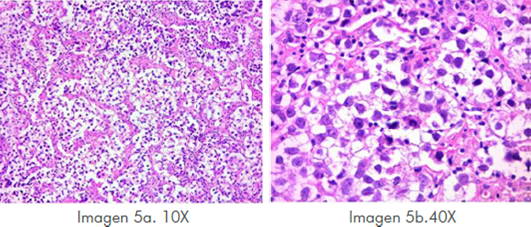

Imagen 5 Aumento 10x, lesión neoplásica de células grandes de redondas a poligonales, citoplasma granular eosinófilo y claro, límites celulares definidos, núcleos grandes y redondos, algunos con cromatina grumosa y nucléolos prominentes, se presenta mitosis atípicas contabilizándose 13 en 10 campos de alto poder. En aumento 40X células agrupadas en nidos, delimitados por septos fibrosos incompletos por los cuales discurren linfocitos maduros no atípicos dispuestos de manera perivascular en los espacios de Virchow Roban.